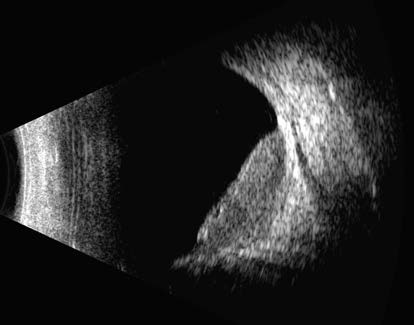

Figure 1 Ocular B-scan ultrasound of choroidal metastasis in the right eye

The image shows a broad-based flat elevation arising from the choroid, with the surface appearing slightly undulated. The internal echogenicity of the lesion is relatively homogeneous, exhibiting medium to low reflectivity.